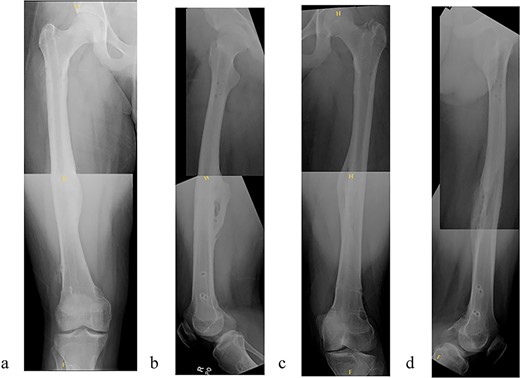

The patient tolerated the procedure well and recovered uneventfully. He was noted to have circumferential osseous healing at 1 year and underwent bilateral femur IMN removal 1.5 years postoperative without complication (Figs 4a–d and 5a–d).

(a) Right femur AP radiograph. (b) Right femur lateral radiograph. (c) Left femur AP radiograph. (d) Left femur lateral radiograph.